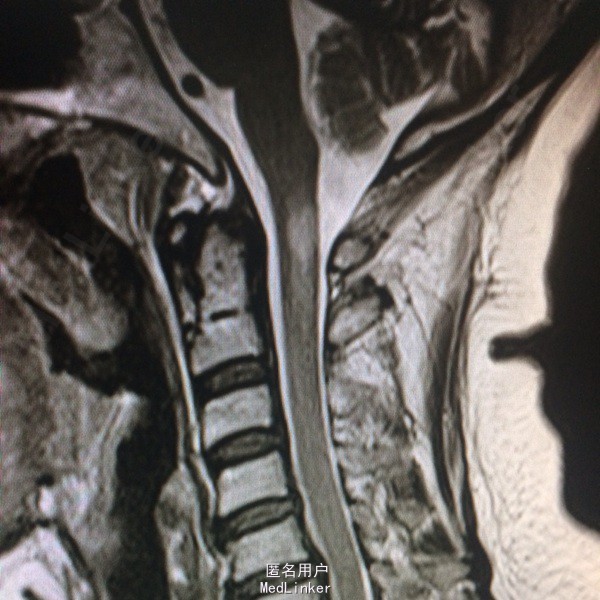

查体:左侧上肢、左侧颈项部、左侧躯干浅感觉减退,左上肢有力5-级,左侧肢体腱反射(+),余(-)。 辅助检查:头颅CT:右侧顶叶、左侧岛叶少许腔隙性梗塞,侧脑室旁脑白质变性,脑萎缩。 入院后查风湿三项:RF:74IU/ml,肌酣:92umol/L。尿酸:362umol/L,胆固醇:6.44mmol/L。糖耐量试验正常。输血四项正常。血沉、自免八项、血管炎3项、血找狼疮细胞均正常。心脏彩超正常。椎动脉彩超、颈动脉彩超正常。肌电图:左侧正中神经腕部节段性损害(感觉纤维受累,脱髓鞘改变),符合左侧腕管综合征电生理改变;左侧正中神经、左侧尺神经F波异常,提示近端神经根(C8-T1)受累,请结合临床。头颅MR:双侧额叶皮层下多发小缺血变性灶,未见急性梗死;右侧椎动脉颅内段较左侧明显细小,颅脑MRA未见异常;右侧桥小脑角增宽,未除蛛网膜囊肿。颈椎MR:颈椎轻度后弓,退行性变:C2/3、C3/4、C4/5、C5/6椎间盘突出(后正中型);C6/7椎间盘膨出,C1椎体水平脊髓内异常信号影,建议增强扫描。增强扫描示:C1水平脊髓内异常信号,脊髓炎与多发性硬化相鉴别。

诊断:急性脊髓炎。 治疗经过:入院后予B1、甲钴胺营养神经,患者症状稍有好转,在完善颈椎MR后考虑急性脊髓炎,予激素冲击治疗。